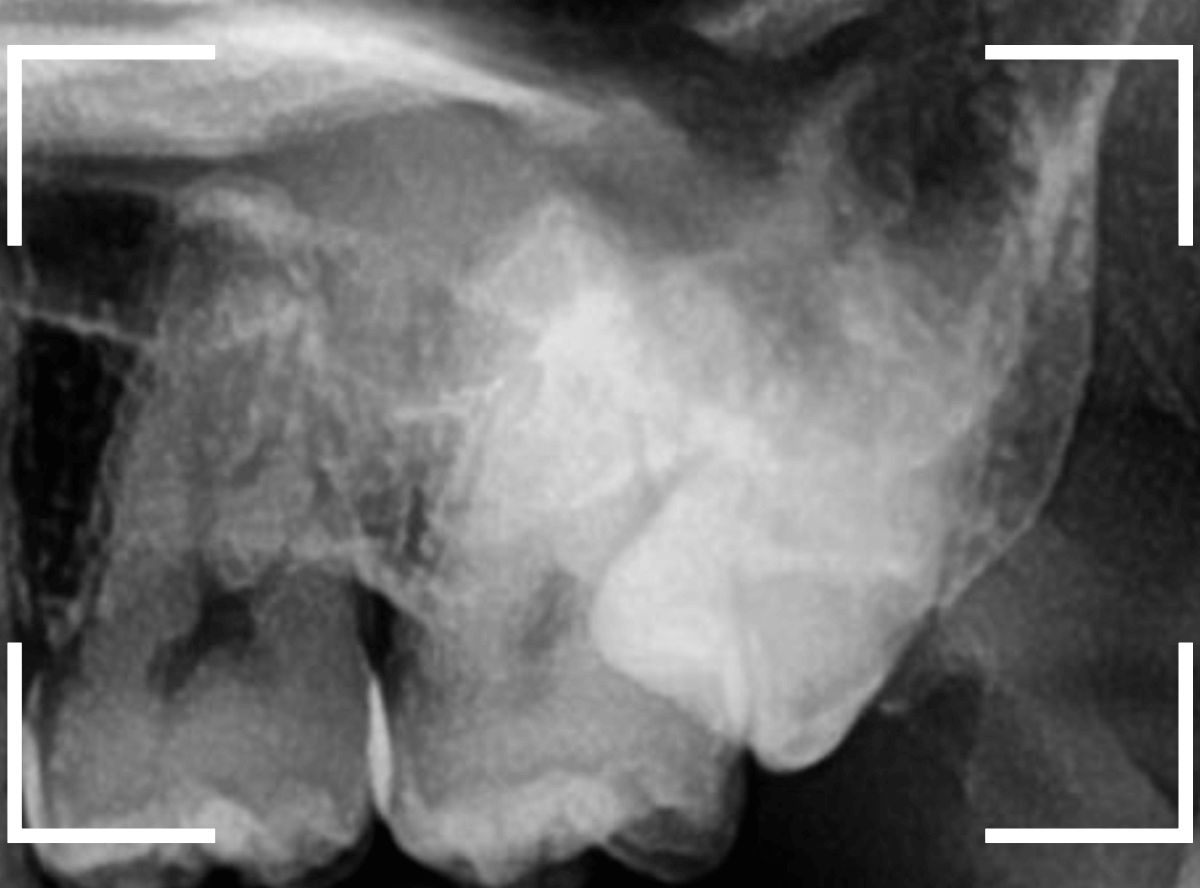

ここでは、比較的簡単なおやしらずの抜歯の例を中心にご紹介します。

このようなおやしらず、あなたはありませんか?